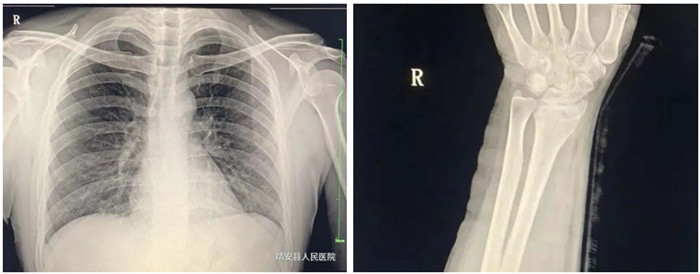

2.脊柱、四肢骨骼及关节

适应症:骨龄检查、先天性发育异常、骨缺血性坏死;骨质疏松、骨髓炎、骨肿瘤、骨关节创伤、骨关节结核、骨关节炎性病变、软组织病变等疾病。

3.胸部

适应症:气管支气管病(支气管结石及异物等);肺部病变(先天性发育异常、炎症、结核、肿瘤等);纵膈病变(气肿、血肿、肿瘤与囊肿等)。